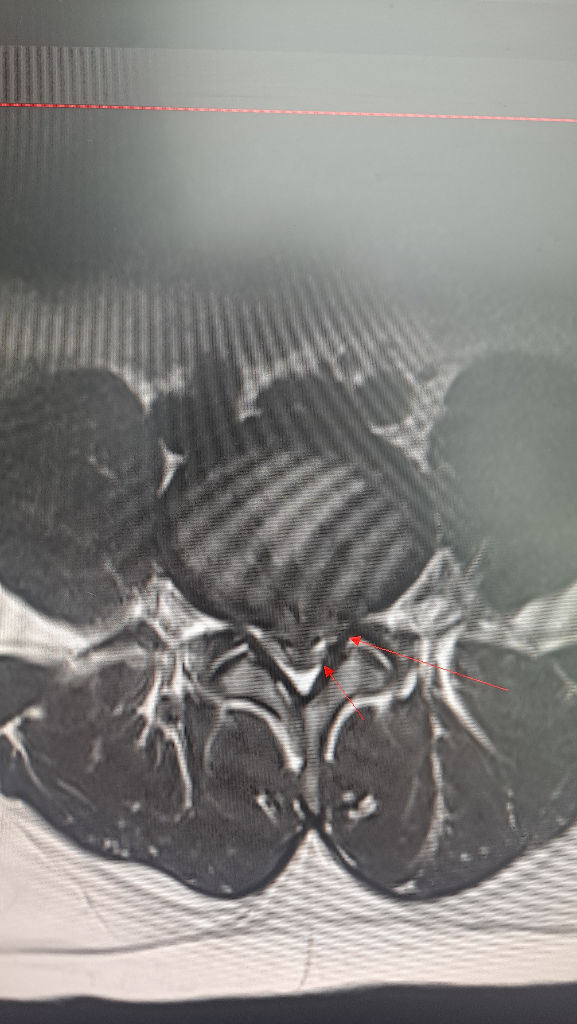

최근에 찍은 mri 결과인데 허리디스크가 심한 상태인가요?

척추전문 병원에 가서 mri를 찍으니 허리디스크라고 합니다. 척추전문병원 의사분께선 원래는 수술을 해야하는 상황인데 아직 제 나이가 젊기도하니 약물이나 시술을 먼저 해본뒤에 그때도 나아지지 않을시 수술을 하자고 하셨구요. 평소에 제가 다니던 동네의 정형외과 의사분께는 여쭤보니 엄청 심한건 아니니 주 1~2회 물리치료 받으면서 상태를 지켜보자 하셨습니다. 디스크가 터진지는 지금 약 10일정도 된거같습니다. 다음달에 대학병원 진료도 예약해놓긴 했는데 혹시 여러분들이 보시기엔 어떤거 같나요?? 보존치료로 충분히 치료가능할까요? 아니면 수술만이 답일까요?ㅠㅠ

• 2번 째 사진

보는 의사마다 소견에 차이가 있을 수 있습니다. 위 사진 두 장만 가지고 명확한 상태를 알 수 없지만 개인적으로 보았을 때에는 디스크가 상당히 많이 탈출하여 척수 신경이 상당히 많이 눌려 있어 심한 상태라고 볼 수 있어 보입니다. 다만 신경학적인 증상이 심하지 않다면 응급하게 수술을 해야한다고 보기는 어렵습니다.